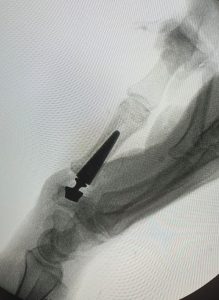

La rizartrosis es la artrosis de la articulación de la base del pulgar.  (Figura 1)

PATOLOGÍAS EN MANO Y DEDOS - RIZARTROSIS Figura 1 - Radiografía de una Rizartrosis

Figura 1 - Radiografía de una Rizartrosis

El diagnóstico de la Rizartrosis se hace mediante a exploración física y ante los hallazgos de dolor e inflamación previamente comentados.  Durante la exploración se puede llegar a notar el roce entre los huesos al mover el pulgar.  Las Radiografías demuestran los signos clásicos de la artrosis: disminución del espacio articular, formación de osteofítos (o espículas óseas) alrededor de la articulación e incluso la subluxación de la articulación (dislocación) en casos avanzados.